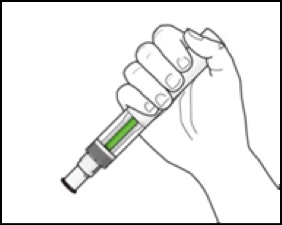

Während der Injektion hören Sie 2 laute Klicks.

Der 1. Klick zeigt an, dass die Injektion begonnen hat. Einige Sekunden danach zeigt ein 2. Klick an, dass die Injektion nahezu abgeschlossen ist.

Sie müssen den Pen fest auf Ihre Haut gedrückt halten, bis ein grüner Indikator im Fenster erscheint und sich nicht mehr bewegt.

6. Beginnen Sie mit der Injektion:

7. Schließen Sie Ihre Injektion ab:

8. Kontrollieren Sie, ob der grüne Indikator im Fenster erscheint: